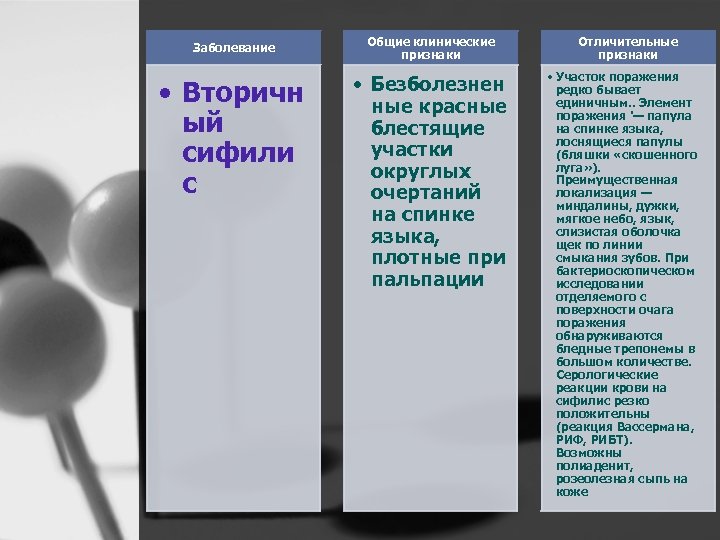

Заболевание • Вторичн ый сифили с Общие клинические признаки • Безболезнен ные красные блестящие участки округлых очертаний на спинке языка, плотные при пальпации Отличительные признаки • Участок поражения редко бывает единичным. . Элемент поражения '— папула на спинке языка, лоснящиеся папулы (бляшки «скошенного луга» ). Преимущественная локализация — миндалины, дужки, мягкое небо, язык, слизистая оболочка щек по линии смыкания зубов. При бактериоскопическом исследовании отделяемого с поверхности очага поражения обнаруживаются бледные трепонемы в большом количестве. Серологические реакции крови на сифилис резко положительны (реакция Вассермана, РИФ, РИБТ). Возможны полиаденит, розеолезная сыпь на коже